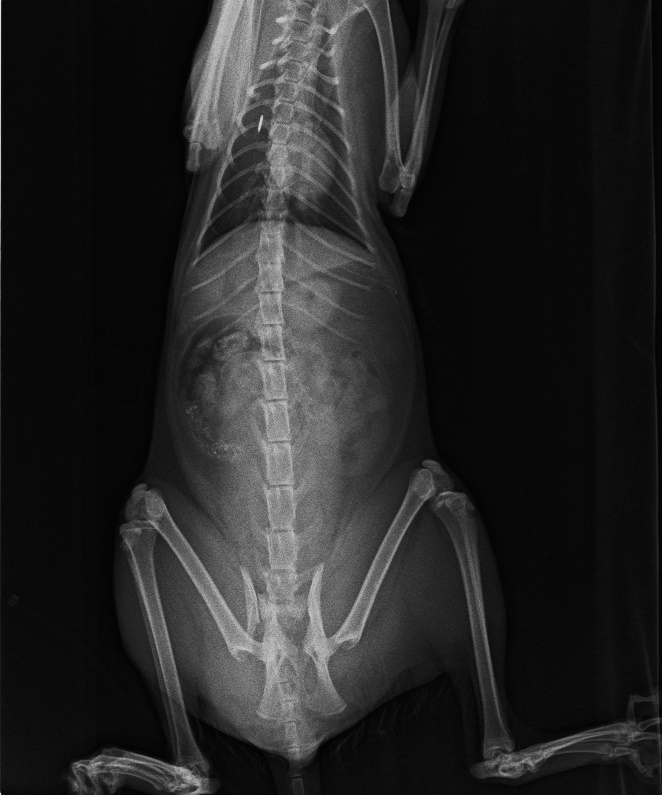

貓咪到院時還會哈氣作勢要咬人,但無法移動身體,檢查腹部有大片瘀青,x光檢查為骨盆骨折,上點滴、抽血,等報告的時候,貓呼吸越來越急促,開始急救打強心針、吸氧,幾分鐘後貓貓已當小天使,整個過程很短很緊迫...